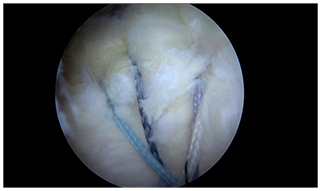

All transosseous techniques offer several permutations and combinations of suture patterns. The simple repair, the box repair, and the X box repair, are demonstrated in Figure 2. These techniques allow for multiple small diameter fixation points to create whichever fixation pattern the surgeon chooses as appropriate.

Figure 2 Various all transosseous repairs: a) simple b) X box c) three tunnel.